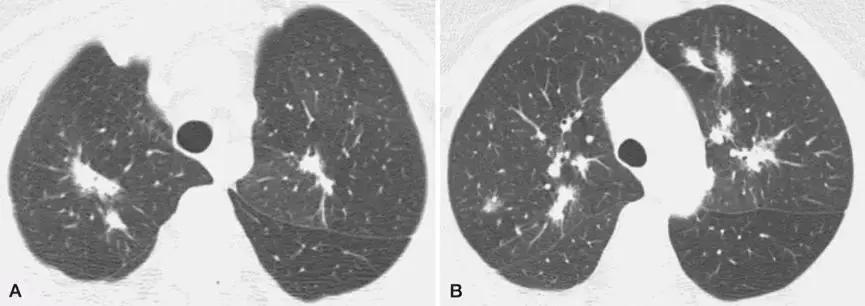

影像学

2、影像学是诊断线索

OP的影像表现:实变(周围、沿支气管血管束):80~95%;磨玻璃影:60~90%;小叶间隔增厚:55%;「反晕征」:20%;结节或团块:15~50%;还有「游走性」的特点。

实变:

中心型

混合型

磨玻璃影:

GGO合并带状实变

GGO,合并周围型及带状实变